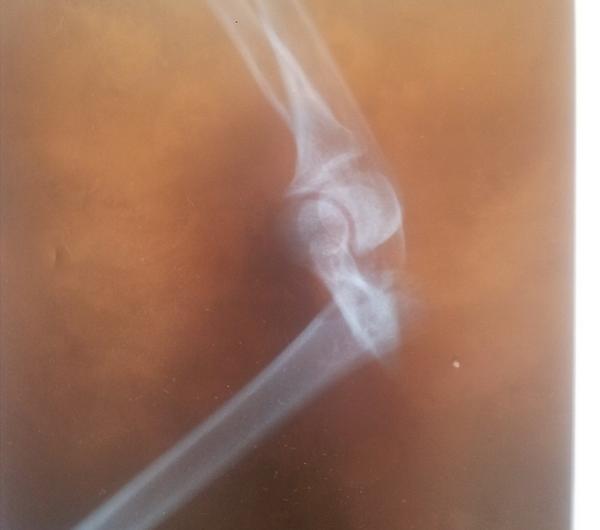

...a do tego kupa nieszczęścia, więc o ciastkach za moment. Niecierpliwi i "brzydliwi" - proszę szybciochem przewinąć do kolejnego zdjęcia ciastek, bo nadchodzące nie będą apetyczne ;) Zachciało mi się jeździć konno, i nie, żeby to pierwszy raz był - jeżdżę, z przerwami, od dziecka. Nie jakoś super-wyczynowo, ale w sumie wiem, gdzie koń ma przód a gdzie tył, i generalnie sobie radzę z całym tym ustrojstwem ;) spaść też mi się zdarzyło, tylko zawsze jakoś...mniej boleśnie. A tym razem, cóż, wbiłam się z całym impetem w ziemię - łokciem. Efekt? Poniższy.

Ta kość, która jest prostopadła, powinna być równoległa, tak. W wyniku wielu dziwnych przygód z naszą ukochaną, polską służbą zdrowia, już tydzień później wyglądało to tak.